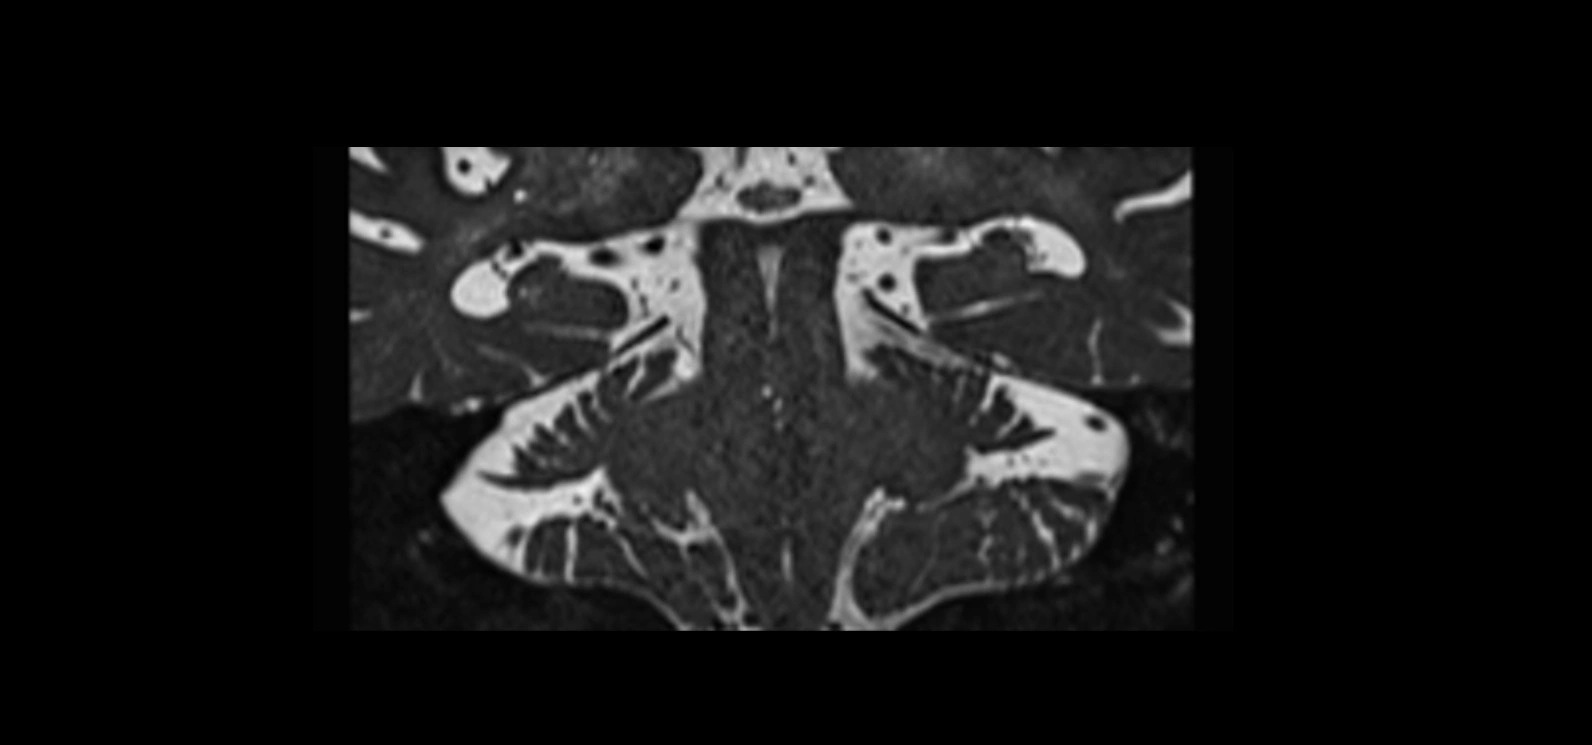

MRI images

image